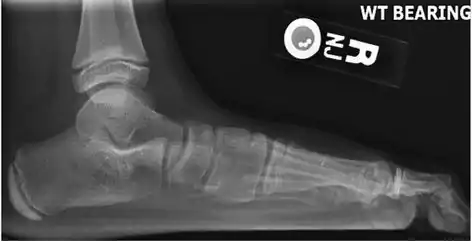

Lateral X-ray of a flat foot with C-sign, which is a bony bridge between the talar dome and sustentaculum tali, in combination with a prominent inferior border of the sustentaculum tali. This represents a talocalcaneal coalition, which is an abnormal connection between the talus and calcaneus and is thought to cause the flat foot deformity in this case.[6]

On plain radiography, flat feet can be diagnosed and graded by several measures, the most important in adults being the talonavicular coverage angle, the calcaneal pitch, and the talar-1st metatarsal angle (Meary's angle).[11] The talonavicular coverage angle is abnormally laterally rotated in flat feet.[11] It is normally up to 7 degrees laterally rotated, so a greater rotation indicates flat feet.[11] Radiographies generally need to be taken on weightbearing feet in order to detect misalignment.[12]